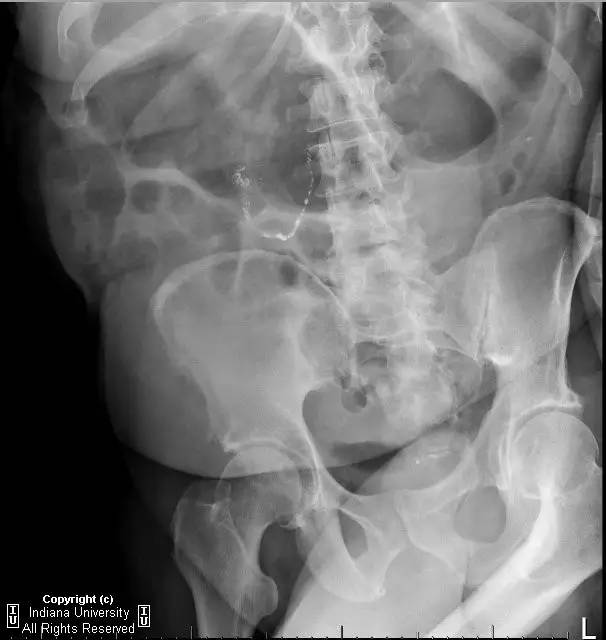

【影像学表现】右侧腹部可见曲线样不透亮区,1周后位置有变化(似进入盲肠)。横结肠显著扩张、充气。CT上扩张原因不明,无明确的梗阻证据。

【诊断】阑尾内对比剂充填